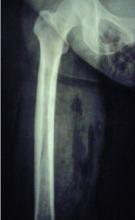

FIGURE 2

Radiograph of thigh and hip area

Note the presence of the soft-tissue gas extending into the patient’s pelvis.

The decision to obtain x-rays of her pelvis and femur was made to assess the extent of her infection (FIGURES 2 AND 3).